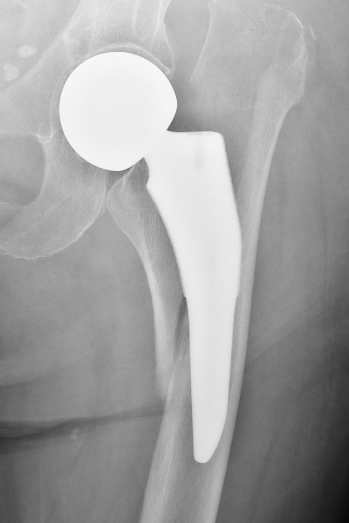

Hemiarthroplasty

Hemiarthroplasty Design Options

Unipolar

- single articulation between prosthesis and acetabulum

Unipolar monoblock

- Austin Moore press fit

- Thompson cemented

- no offset options

Modular unipolar

Based on standard THR concepts

- alternative offset options

- neck length options

- cemented or uncemented